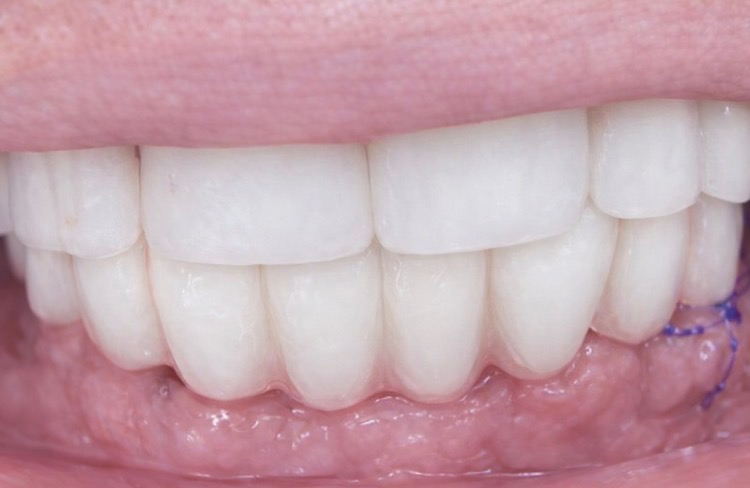

Peut-on remplacer ses dents en une seule journée ? Oui. Grâce à l’implantologie immédiate, il est possible de réaliser les extractions, poser les implants et fixer un bridge provisoire dans la même journée.

Exemple réel : chirurgie terminée à 11h — sourire fixé à 16h.

3. Fixation d’un bridge provisoire vissé le jour même.

– Esthétique immédiate

L’implantologie immédiate permet aujourd’hui de transformer un sourire en quelques heures : entrer le

matin sans dents fixes et repartir l’après-midi avec un sourire stable et esthétique.

Cas clinique réalisé au sein du réseau Labelia, Implantologie Dentaire